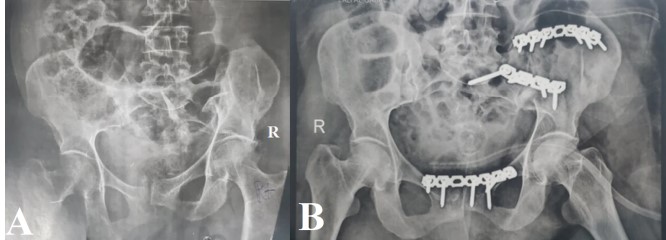

Autogenous structural bone graft reconstruction of uncontained significant medial proximal tibial bone defects in primary total knee arthroplasty

Anwar Abdulqader Mughalles, , Abdulrakib Saleh Almirah, Abdulkareem Esmail Alsabri, Marwan Mohammed Farhan, Ghamdan Gamal Alkholidy (Author)

489 - 496